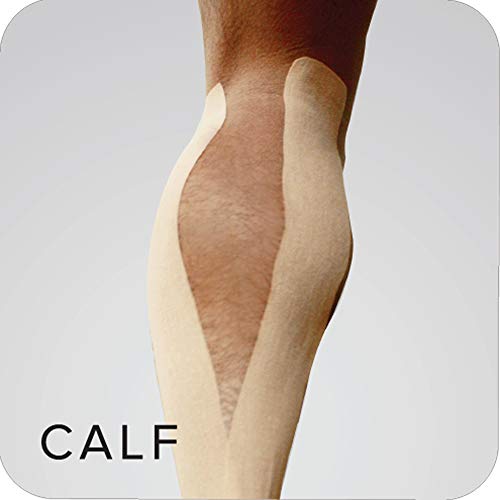

- Rehabilite edilmek istenen bölgeye hem kinesyolojik tekniklerle hem klinik bantlama teknikleriyle uygulanır.

- Ödem kotrolü, hematom, nekrotik dokuların olumlu yönde geliştirilmesi, yumsak doku hasarlarının kondüsyonunu gelişimi ve tüm bunların yaparken hareket kısıtlayabilen için yeni bir teknoloji ürünüdür.